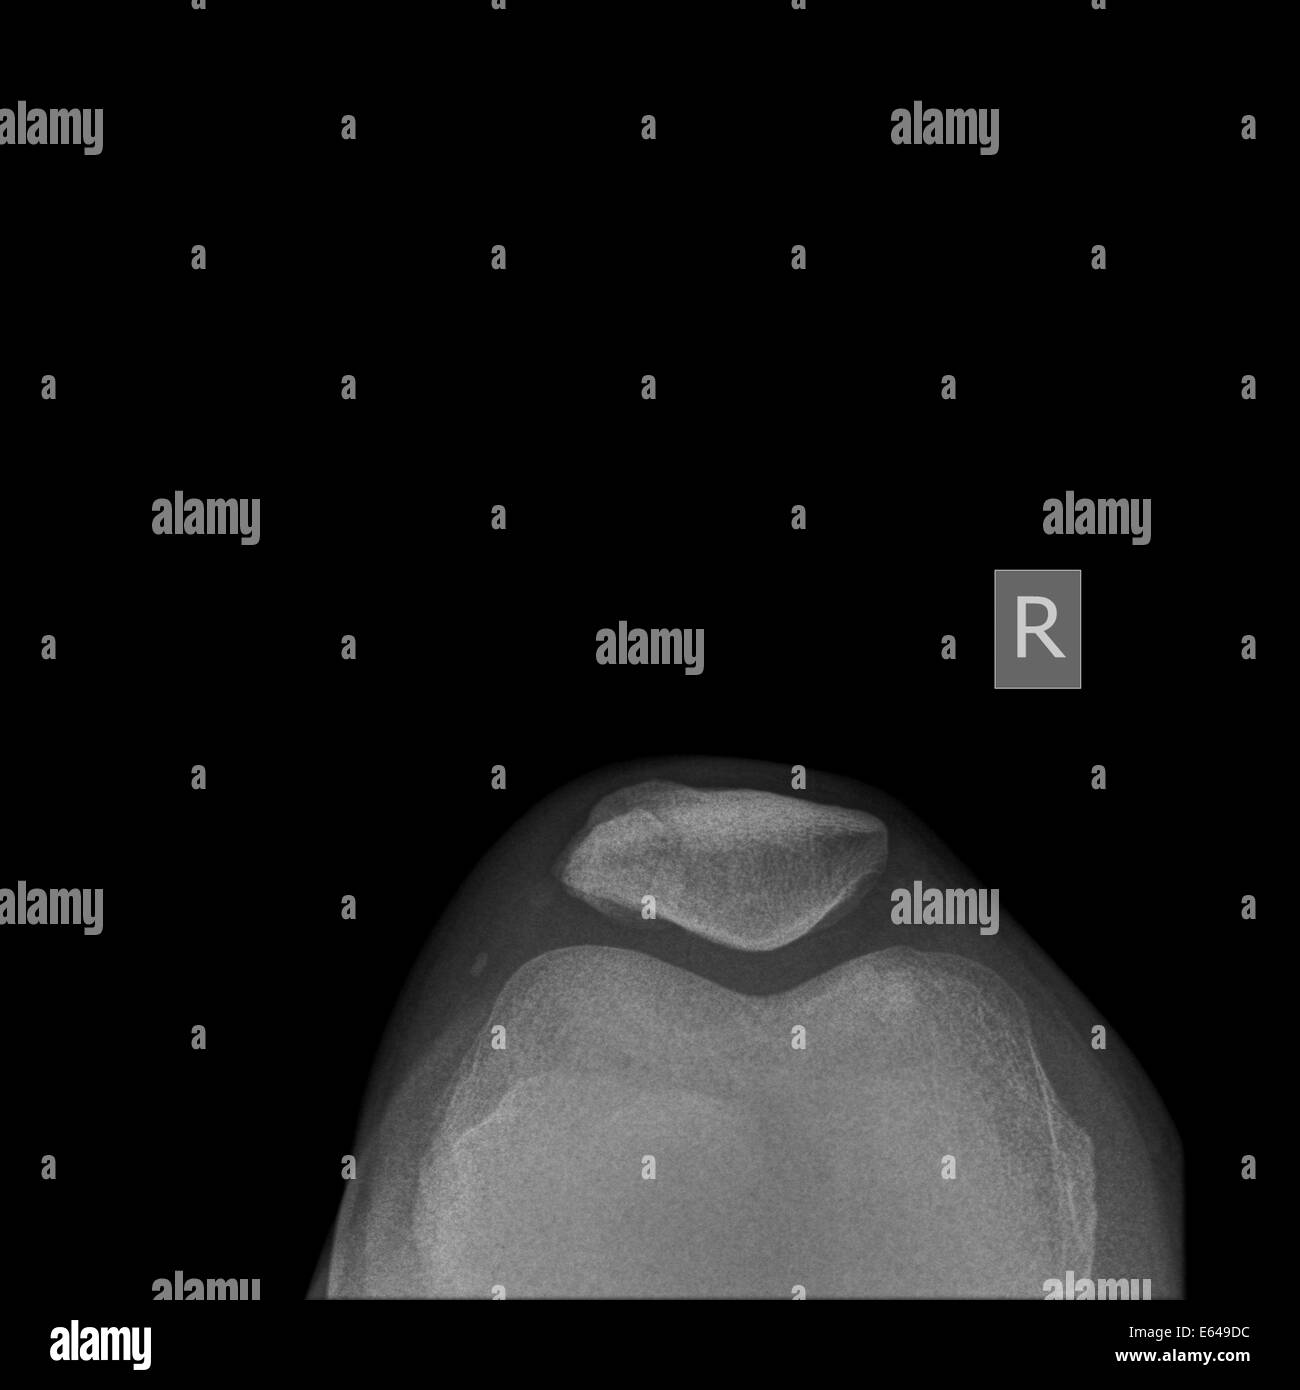

From www.alamyimages.fr

Fracture de la rotule Banque d'images noir et blanc Alamy Fracture De La Rotule Du Genou  Le traitement d'une fracture du genou dépend de sa gravité : Lors de ce type de traumatisme, l’articulation saigne de l’intérieur, ce qui provoque dans tous les cas un gonflement à l’avant de l’articulation. Le trait de fracture est le plus fréquemment transverse, en plein corps de la rotule, traversant ainsi la surface cartilagineuse, il s’agit donc d’une articulaire pouvant. Fracture De La Rotule Du Genou.

Xray du genou de femme de 55 ans présentant une fracture de la rotule Photo Stock Alamy Fracture De La Rotule Du Genou   la fracture de la rotule, ou fracture patellaire, se traduit généralement par une douleur intense et l’incapacité à mobiliser le genou. Le trait de fracture est le plus fréquemment transverse, en plein corps de la rotule, traversant ainsi la surface cartilagineuse, il s’agit donc d’une articulaire pouvant causer ou favoriser l.    — vous avez une fracture de la. Fracture De La Rotule Du Genou.